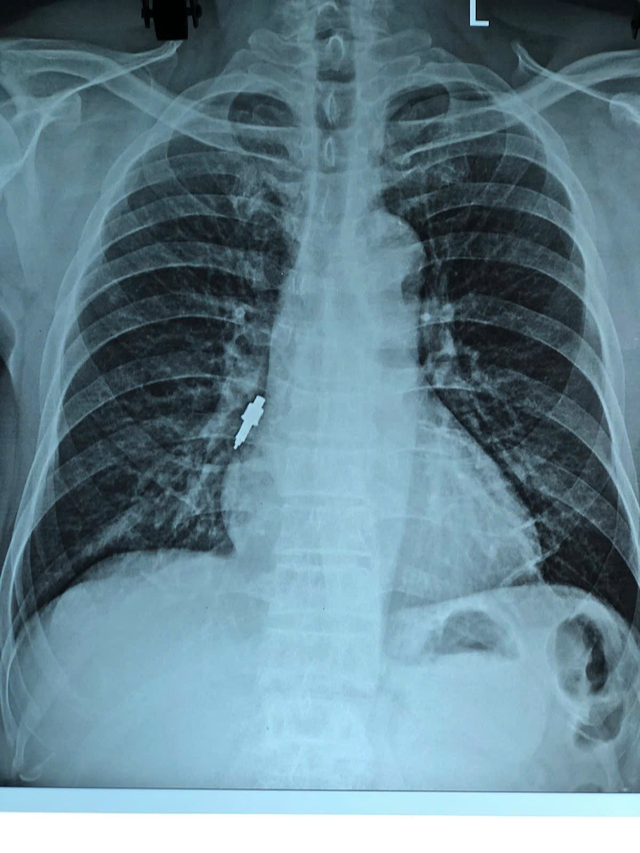

Qua khai thác bệnh nhân cho biết cách đây khoảng hai tuần có thực hiện thủ thuật đặt Implant tại một phòng khám răng tư nhân. Trong quá trình thao tác, bác sĩ nha khoa thông báo có đánh mất một dụng cụ nhưng không xác định được vị trí rơi. Sau khi về, bệnh nhân xuất hiện ho nhẹ kéo dài và tăng dần nên đến bệnh viện thăm khám. Kết quả chụp X-quang cho thấy người bệnh có dị vật nằm tại phế quản phải. Quá trình nội soi cấp cứu trường hợp trên gặp nhiều khó khăn do dị vật to, trơn, mắc sâu trong phế quản.

Dị vật mắc sâu trong phế quản của bệnh nhân.